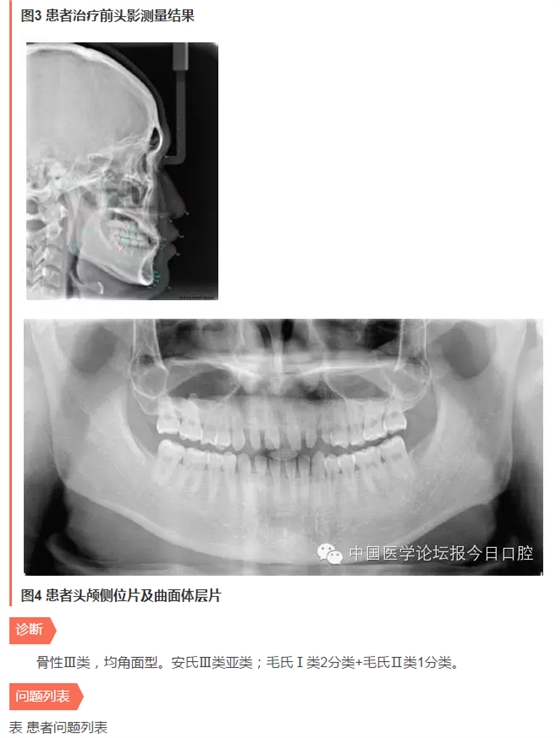

首頁(yè)各類病例 口腔學(xué)科交融之正畸修復(fù)聯(lián)合治療病例——厲松教授

口腔學(xué)科交融之正畸修復(fù)聯(lián)合治療病例——厲松教授